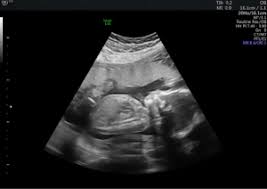

Week 20 Ultrasound What It Would Look Like Parents

Week 20 Ultrasound What It Would Look Like Parents from imagesvc.meredithcorp.io

For the baby's birth weight, take the number from. A baby born at 24 or 25 weeks will weigh less than a baby born at 28 or 29 weeks. She is currently at 30 weeks and both the twins fetel weight & abdominal circumference is not at the expected range for the week. At 20 weeks pregnant, baby is the size of a banana. At the end of the pregnancy, the baby can range from under five pounds to over nine pounds. This is because a baby's legs are curled up against his torso during the first half of pregnancy and very hard to measure. They weigh about 10.2 ounces and measure about 6.5 inches from crown to rump. She said measurements were all perfect for 20 weeks on the dot.

Keeping you in my thoughts! I just had my 20 week u/s. It increases with time and weighs around 1.4lb at birth. While the baby is still growing, the growth will be tapered. My baby was 10oz also at 20 weeks and ob wasn't concerned at all. (crown to rump measurements) gestational age. For female infants, the world health organization (who) estimates babies must weigh between 6.6 to 12.6 pounds at 1 month; They weigh about 10.2 ounces and measure about 6.5 inches from crown to rump. But baby weighs 13 oz already. For the first half of pregnancy (when a baby's legs are curled up against his torso), measurements are taken from the top of his head to his bottom, or from crown to rump. but starting at 20 weeks, he's measured from head to toe. This is because a baby's legs are curled up against his torso during the first half of pregnancy and very hard to measure. Between about 25 to 35 pounds or 11.5 and 16 kg extra weight during pregnancy. We go for a check up in a few days to see how she's grown!